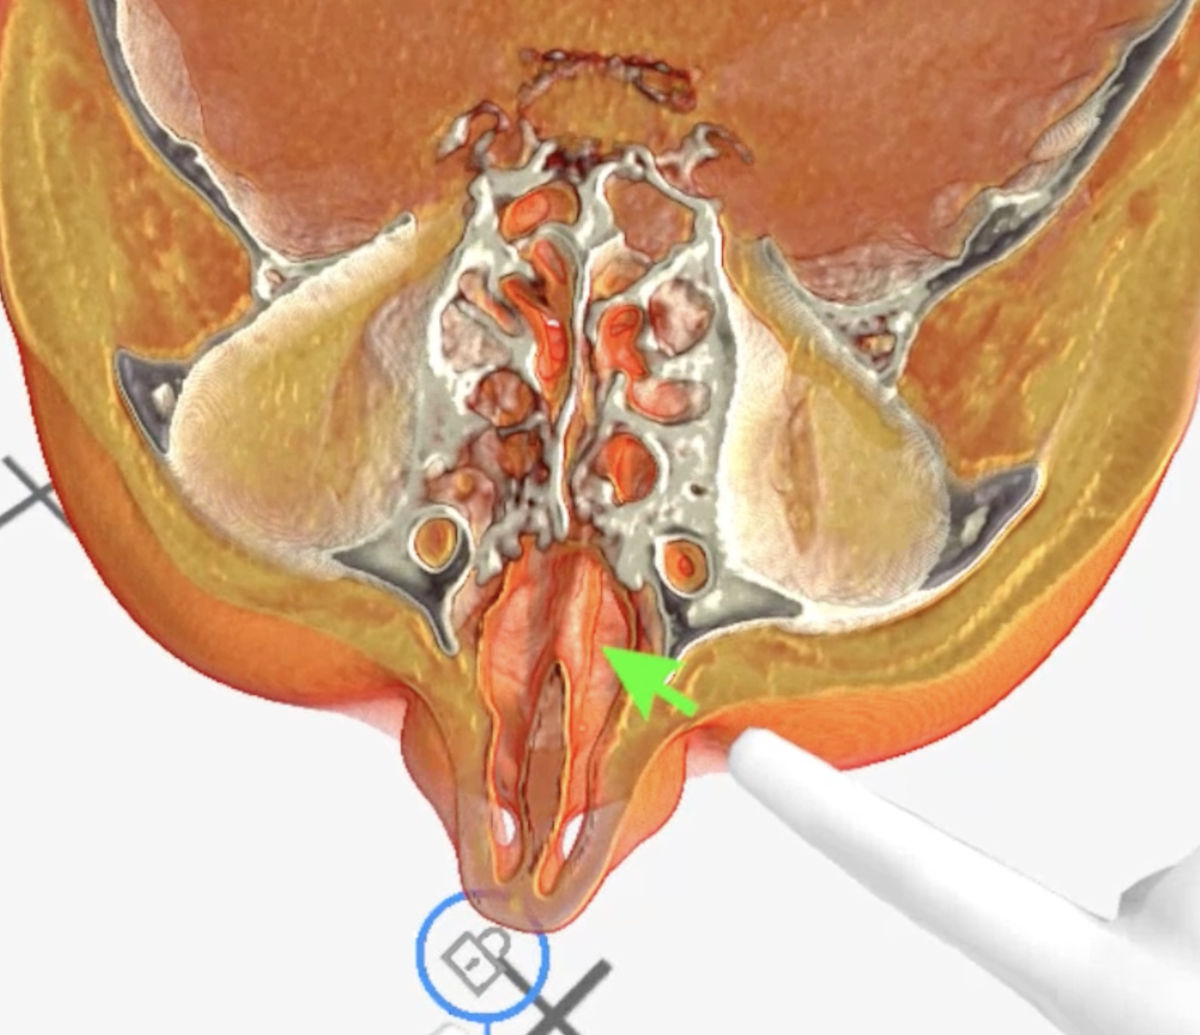

These lesions were visualized with volumetric 3D-rendering of the CT and MRI images with Medical Imaging XR software (MedicalHolodeck, Switzerland), which allowed for better evaluation of the pathologically altered craniofacial anatomy (Fig. 6-9).

Figure 8. Medical Imaging XR 3D-rendered CT shows nasal septum defect (green arrow).